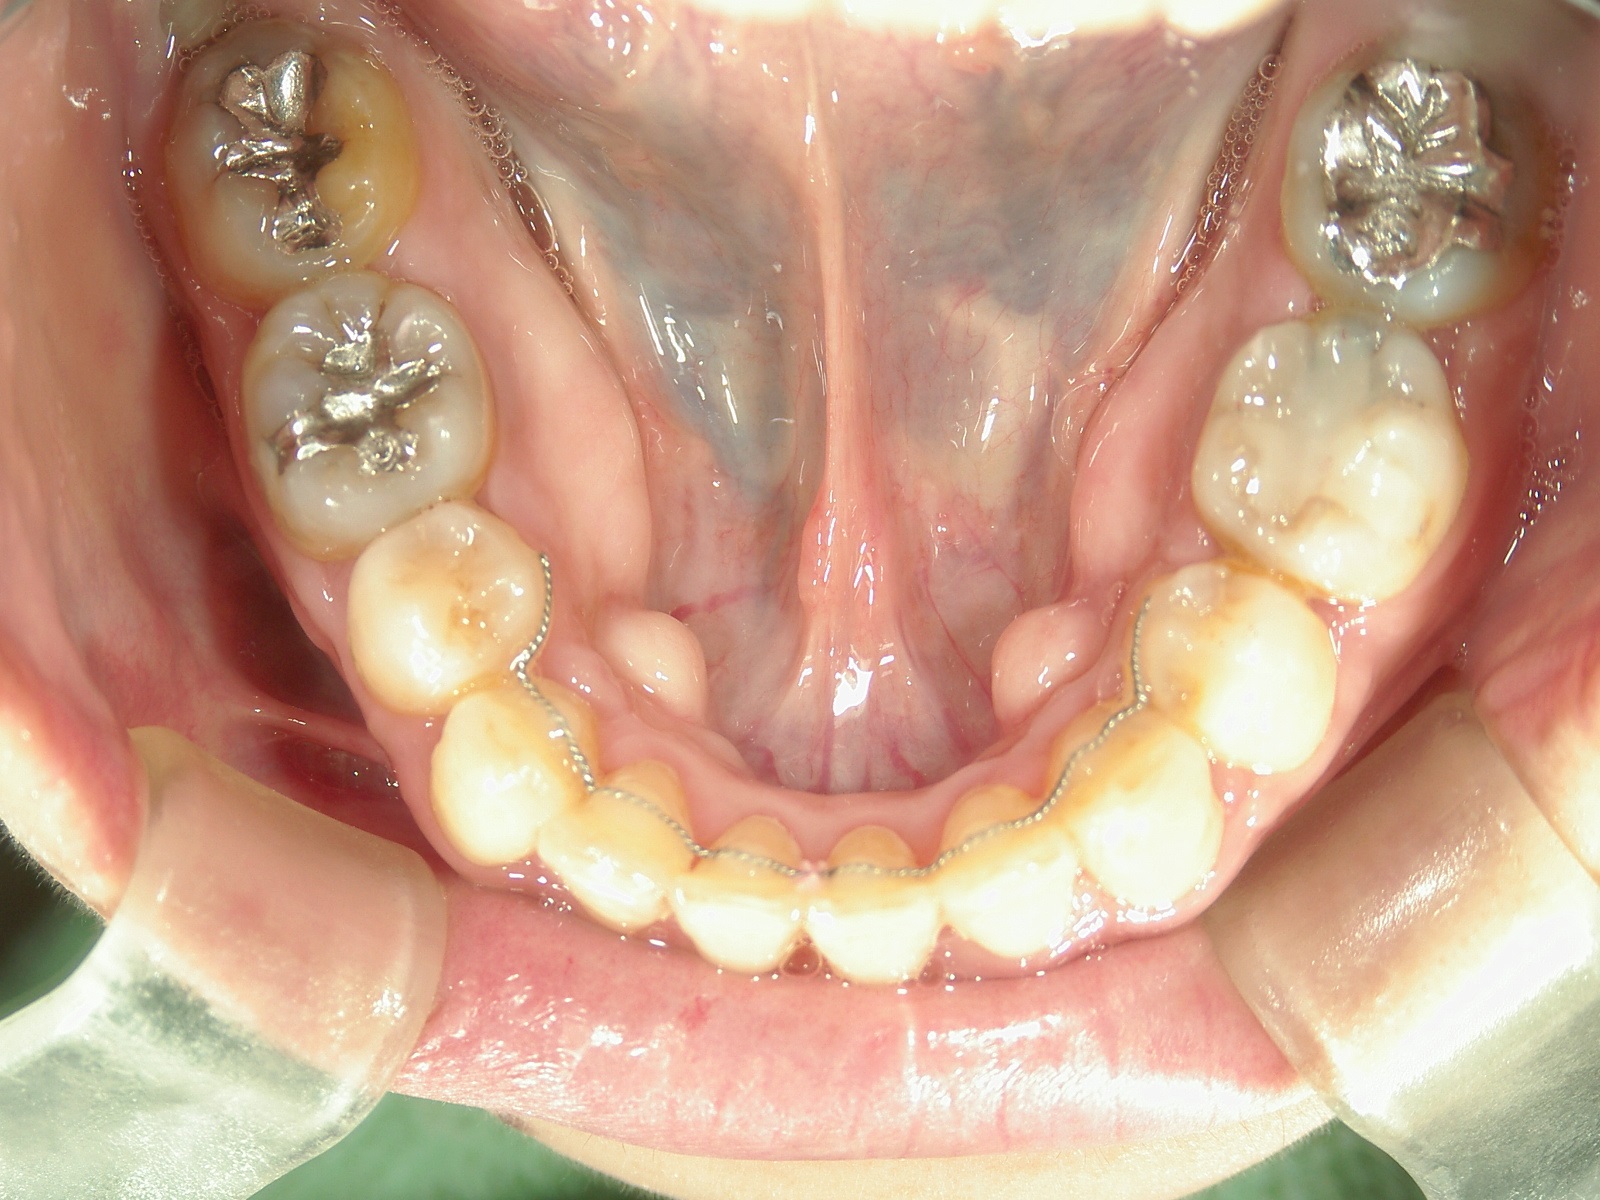

全顎ワイヤー矯正 症例(70)

主訴: 8年前の事故でぶつけて歯根吸収していた為、前突・叢生が気になる。

左右下 第一小臼歯2本、左上 第一大臼歯1本、右上 前歯1本を抜歯。